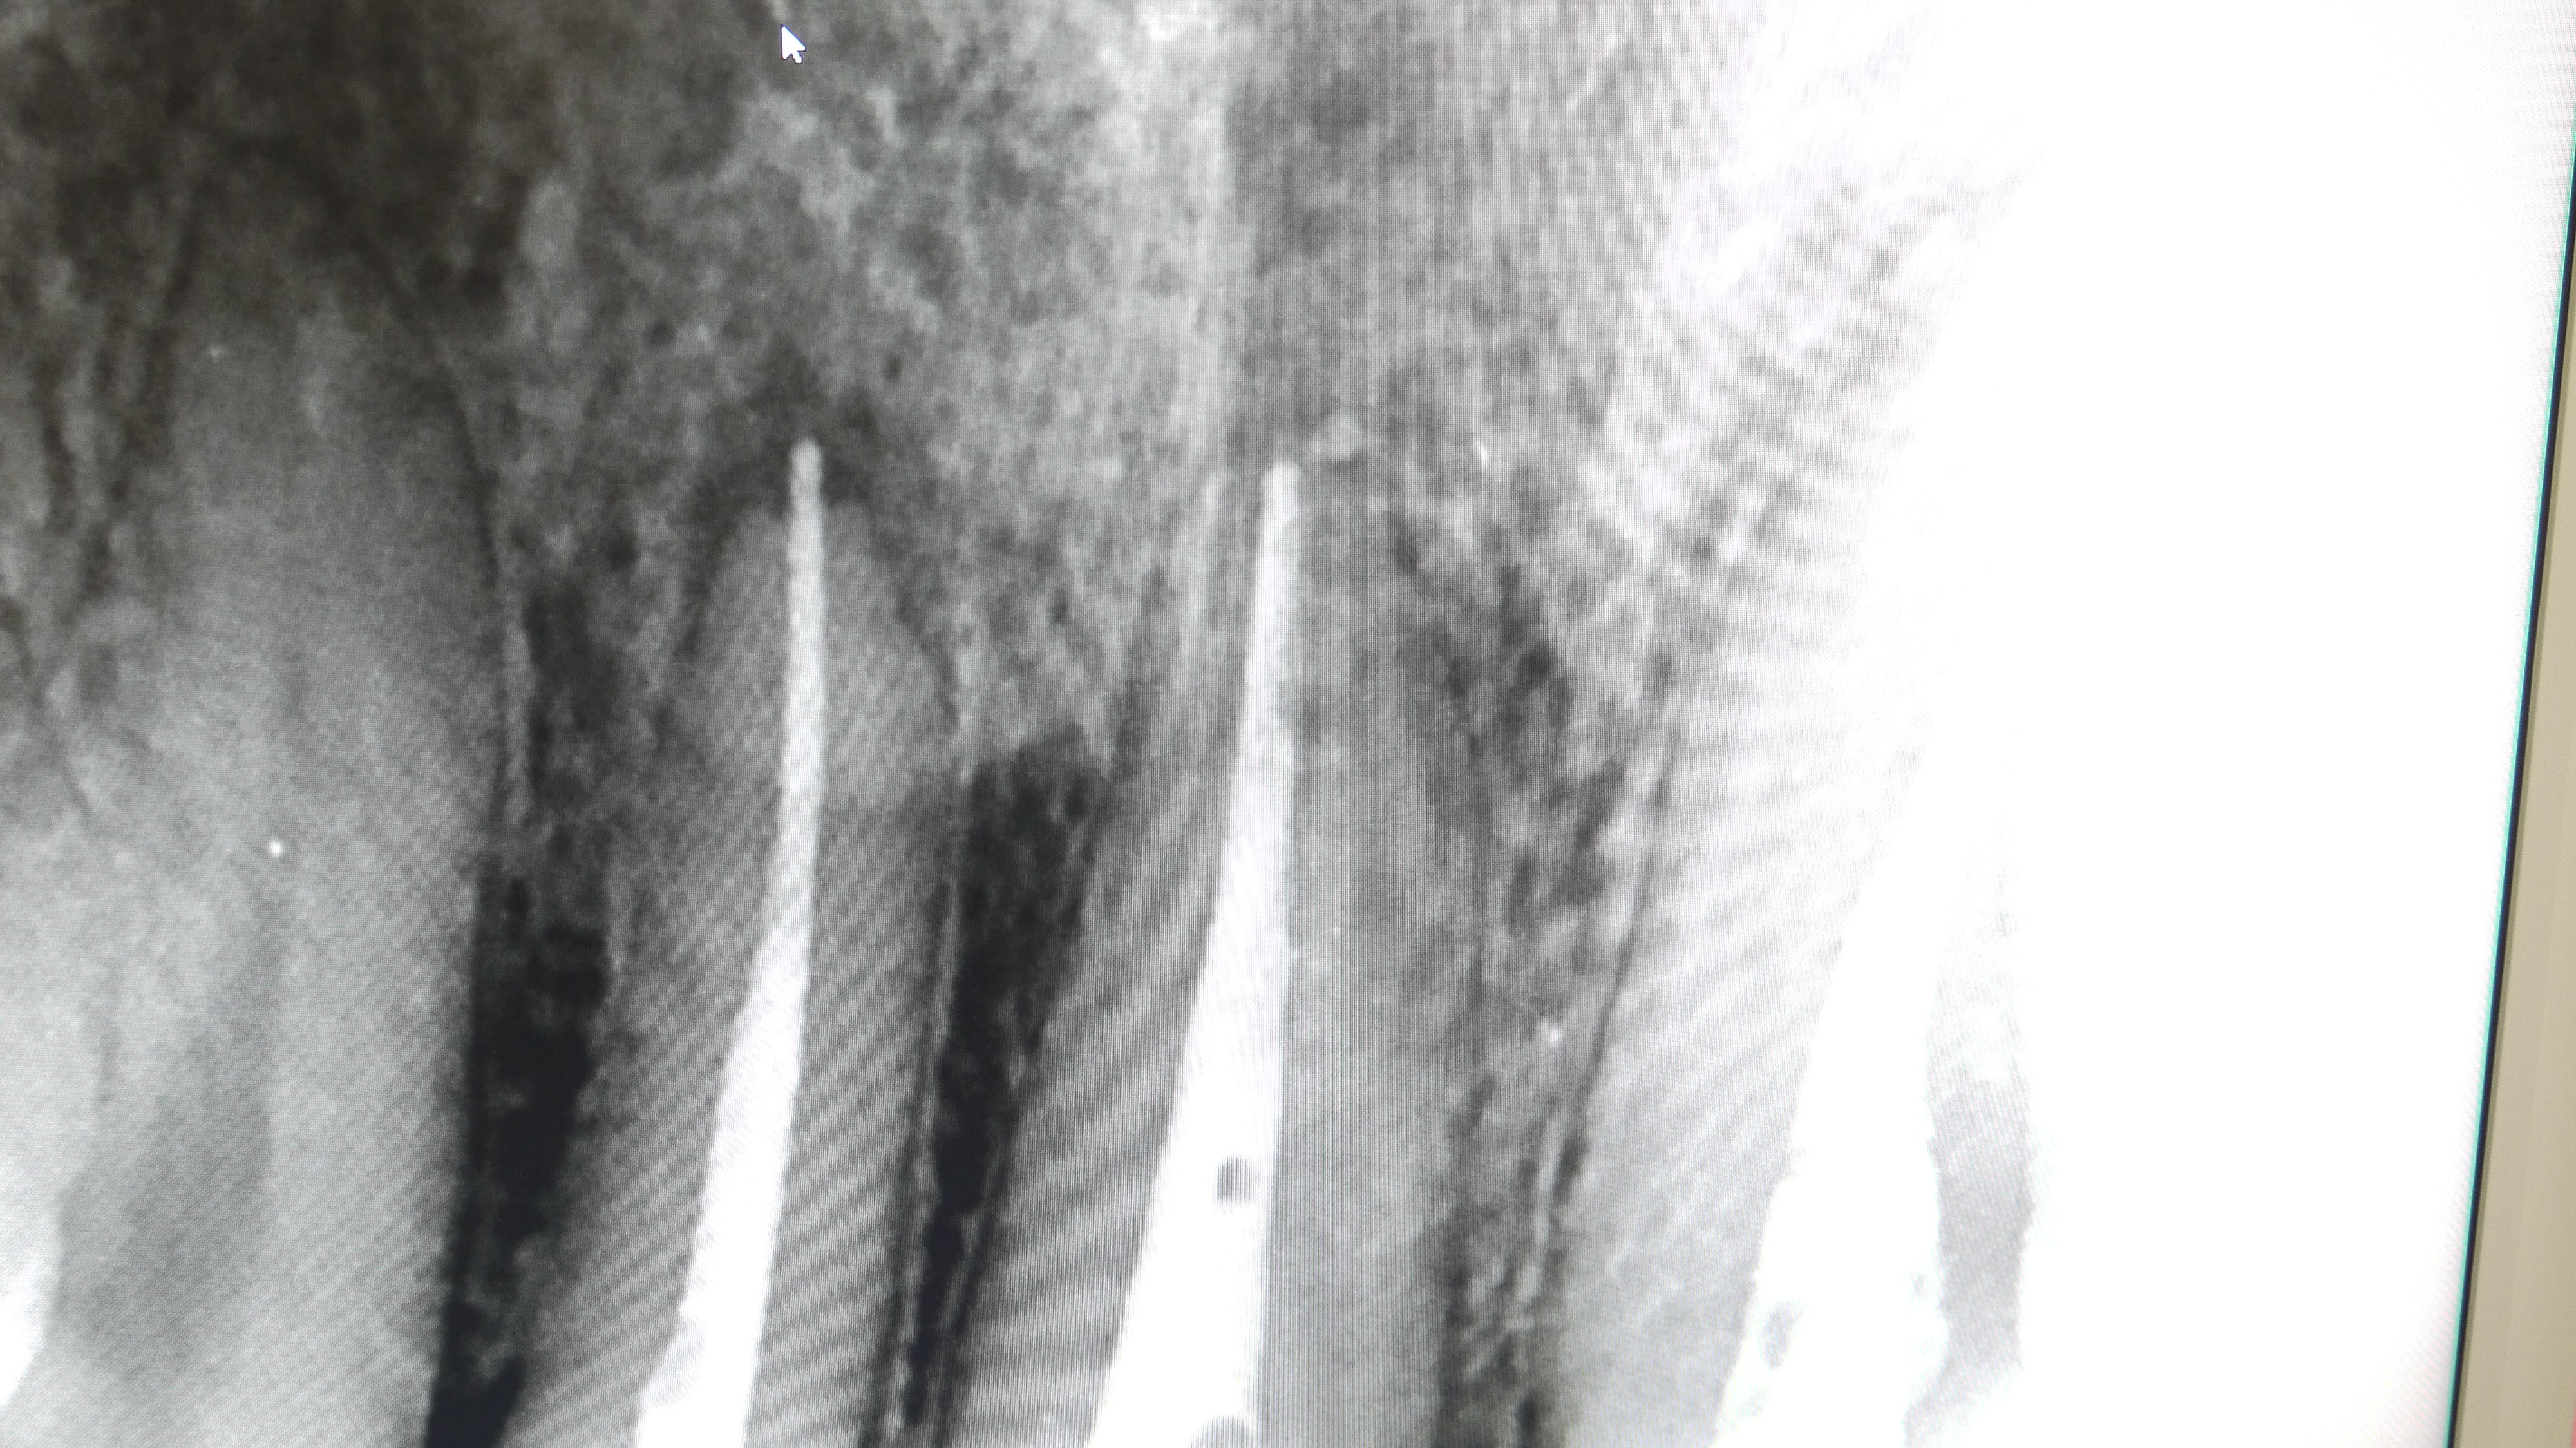

根管の中に薬(ガッタパーチャとシーラー)をつめていきます。(根管処置)

この際、根の長さぴったりまで加圧しながら薬を詰めていくことが

腫れの再発を防ぐために最も重要です。